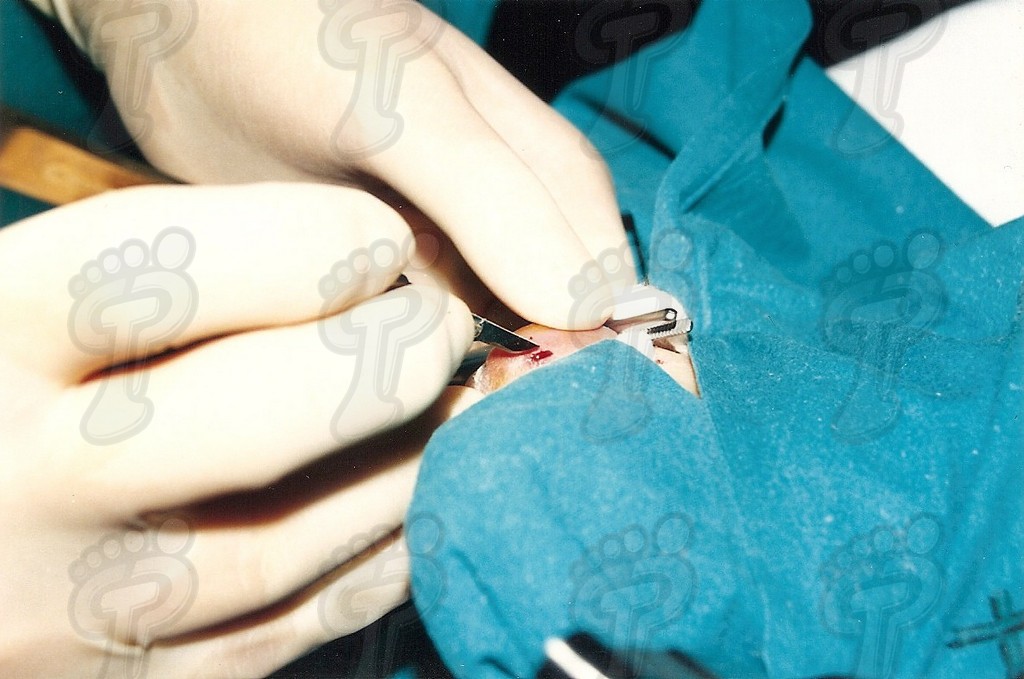

Se realiza la técnica mediante anestesia troncular y sin hemostasia (o al menos, tras el legrado). Hacemos una incisión transversal en la zona dorsoplantar distal a dos o tres milímetros de la prominencia ósea, se introduce el bisturí perpendicularmente al eje de la falange hasta tocar hueso, y a partir de ahí, se desciende bien próximo al tejido ósea para separar partes blandas y delimitar la exóstosis. No se debe incidir lateralmente porque podríamos dañar el paquete neurovascular. Se introduce un cincel separando tejido óseo blando y se delimita la prominencia ósea, la cual suele ser mayor que en la radiografía debido a una zona cartilaginosa radiotransparente. Se legra exhaustivamente con la lima de proximal a distal y de profundidad a superficie (sin vaivén). En las primeras capas (cortical y periostio) notamos que la lima patina y a continuación percibimos el raspado óseo. Con el pulgar de la mano pasiva presionamos de proximal a distal para que salgan al exterior las partículas óseas legradas. Legramos ampliamente ya que al producir un traumatismo óseo siempre hay una regeneración ósea debida a la rica red capilar superficial. Si no lo hacemos así, se puede volver a regenerar el tejido óseo produciendo de nuevo y en poco tiempo la exóstosis. Favorecemos el sangrado de la zona para ayudar a eliminar posibles partículas óseas. Lavamos abundantemente la incisión con suero fisiológico. Volvemos a realizar otra radiografía dorsoplantar intraquirúrgica, a ser posible en la misma posición pre-quirúrgica (la radiografía oblícua no da imagen real del tamaño de exóstosis y la lateral no muestra nada). Hemos de observar en la radiografía que la cabeza de la falange proximal está en el mismo plano que la base de la falange media, ya que si no puede producir algias post-operatorias. Si observamos una nebulosa en la radiografía, son pequeñas partículas o fragmentos óseos que deben drenarse mediante lavados ya que si no se reagrupan y vuelven a regenerar la exóstosis de nuevo. Se han de hacer lavados y radiografías hasta quedar la zona totalmente limpia de fragmentos óseos. Infiltramos anestésico y corticoides en proporción 9 a 1. No hemos de abusar del corticoide porque al entrar en contacto con la trabécula ósea que hemos dejado como capa externa, puede producir problemas graves post-operatorios, tales como la osteoporosis. Se aconseja primero cargar el corticoide y luego el anestésico para evitar que se cristalice el corticoide produciendo trastornos yatrogénicos. Una vez infiltrada la mezcla, presionamos la herida proximal a distal para drenarla ya que sólo nos interesa el efecto farmacológico antiinflamatorio. A continuación, suturamos con seda 5/0 mediante dos puntos simples. En el caso que os mostramos ferulizamos el quinto dedo con una gasa de “U”, impidiendo así la movilización dorsoplantar y, para más sujeción, se une al cuarto dedo con la ayuda de un vendaje circular. Puede impregnarse en yodo la férula en forma de “U” para darle mayor rigidez o consistencia y por lo tanto, menor movilidad al quinto dedo. El vendaje debe ser semicompresivo alineado el dedo. Aconsejamos al paciente reposo durante 48 horas. Pautamos la analgesia correspondiente, y le informamos de las actuaciones que debe efectuar ante determinadas anomalías. Retiramos el apósito quirúrgico a las 48 horas y se cura con povidona yodada dos veces al día (mañana y tarde). Enseñamos al paciente a hacer el vendaje en forma de “U”. A los siete días retiramos la sutura y confeccionamos una cresta de silicona, que debería emplear hasta alcanzar la normalidad articular. Dicha silicona ha de ser utilizada durante un período que oscile entre seis meses a un año.